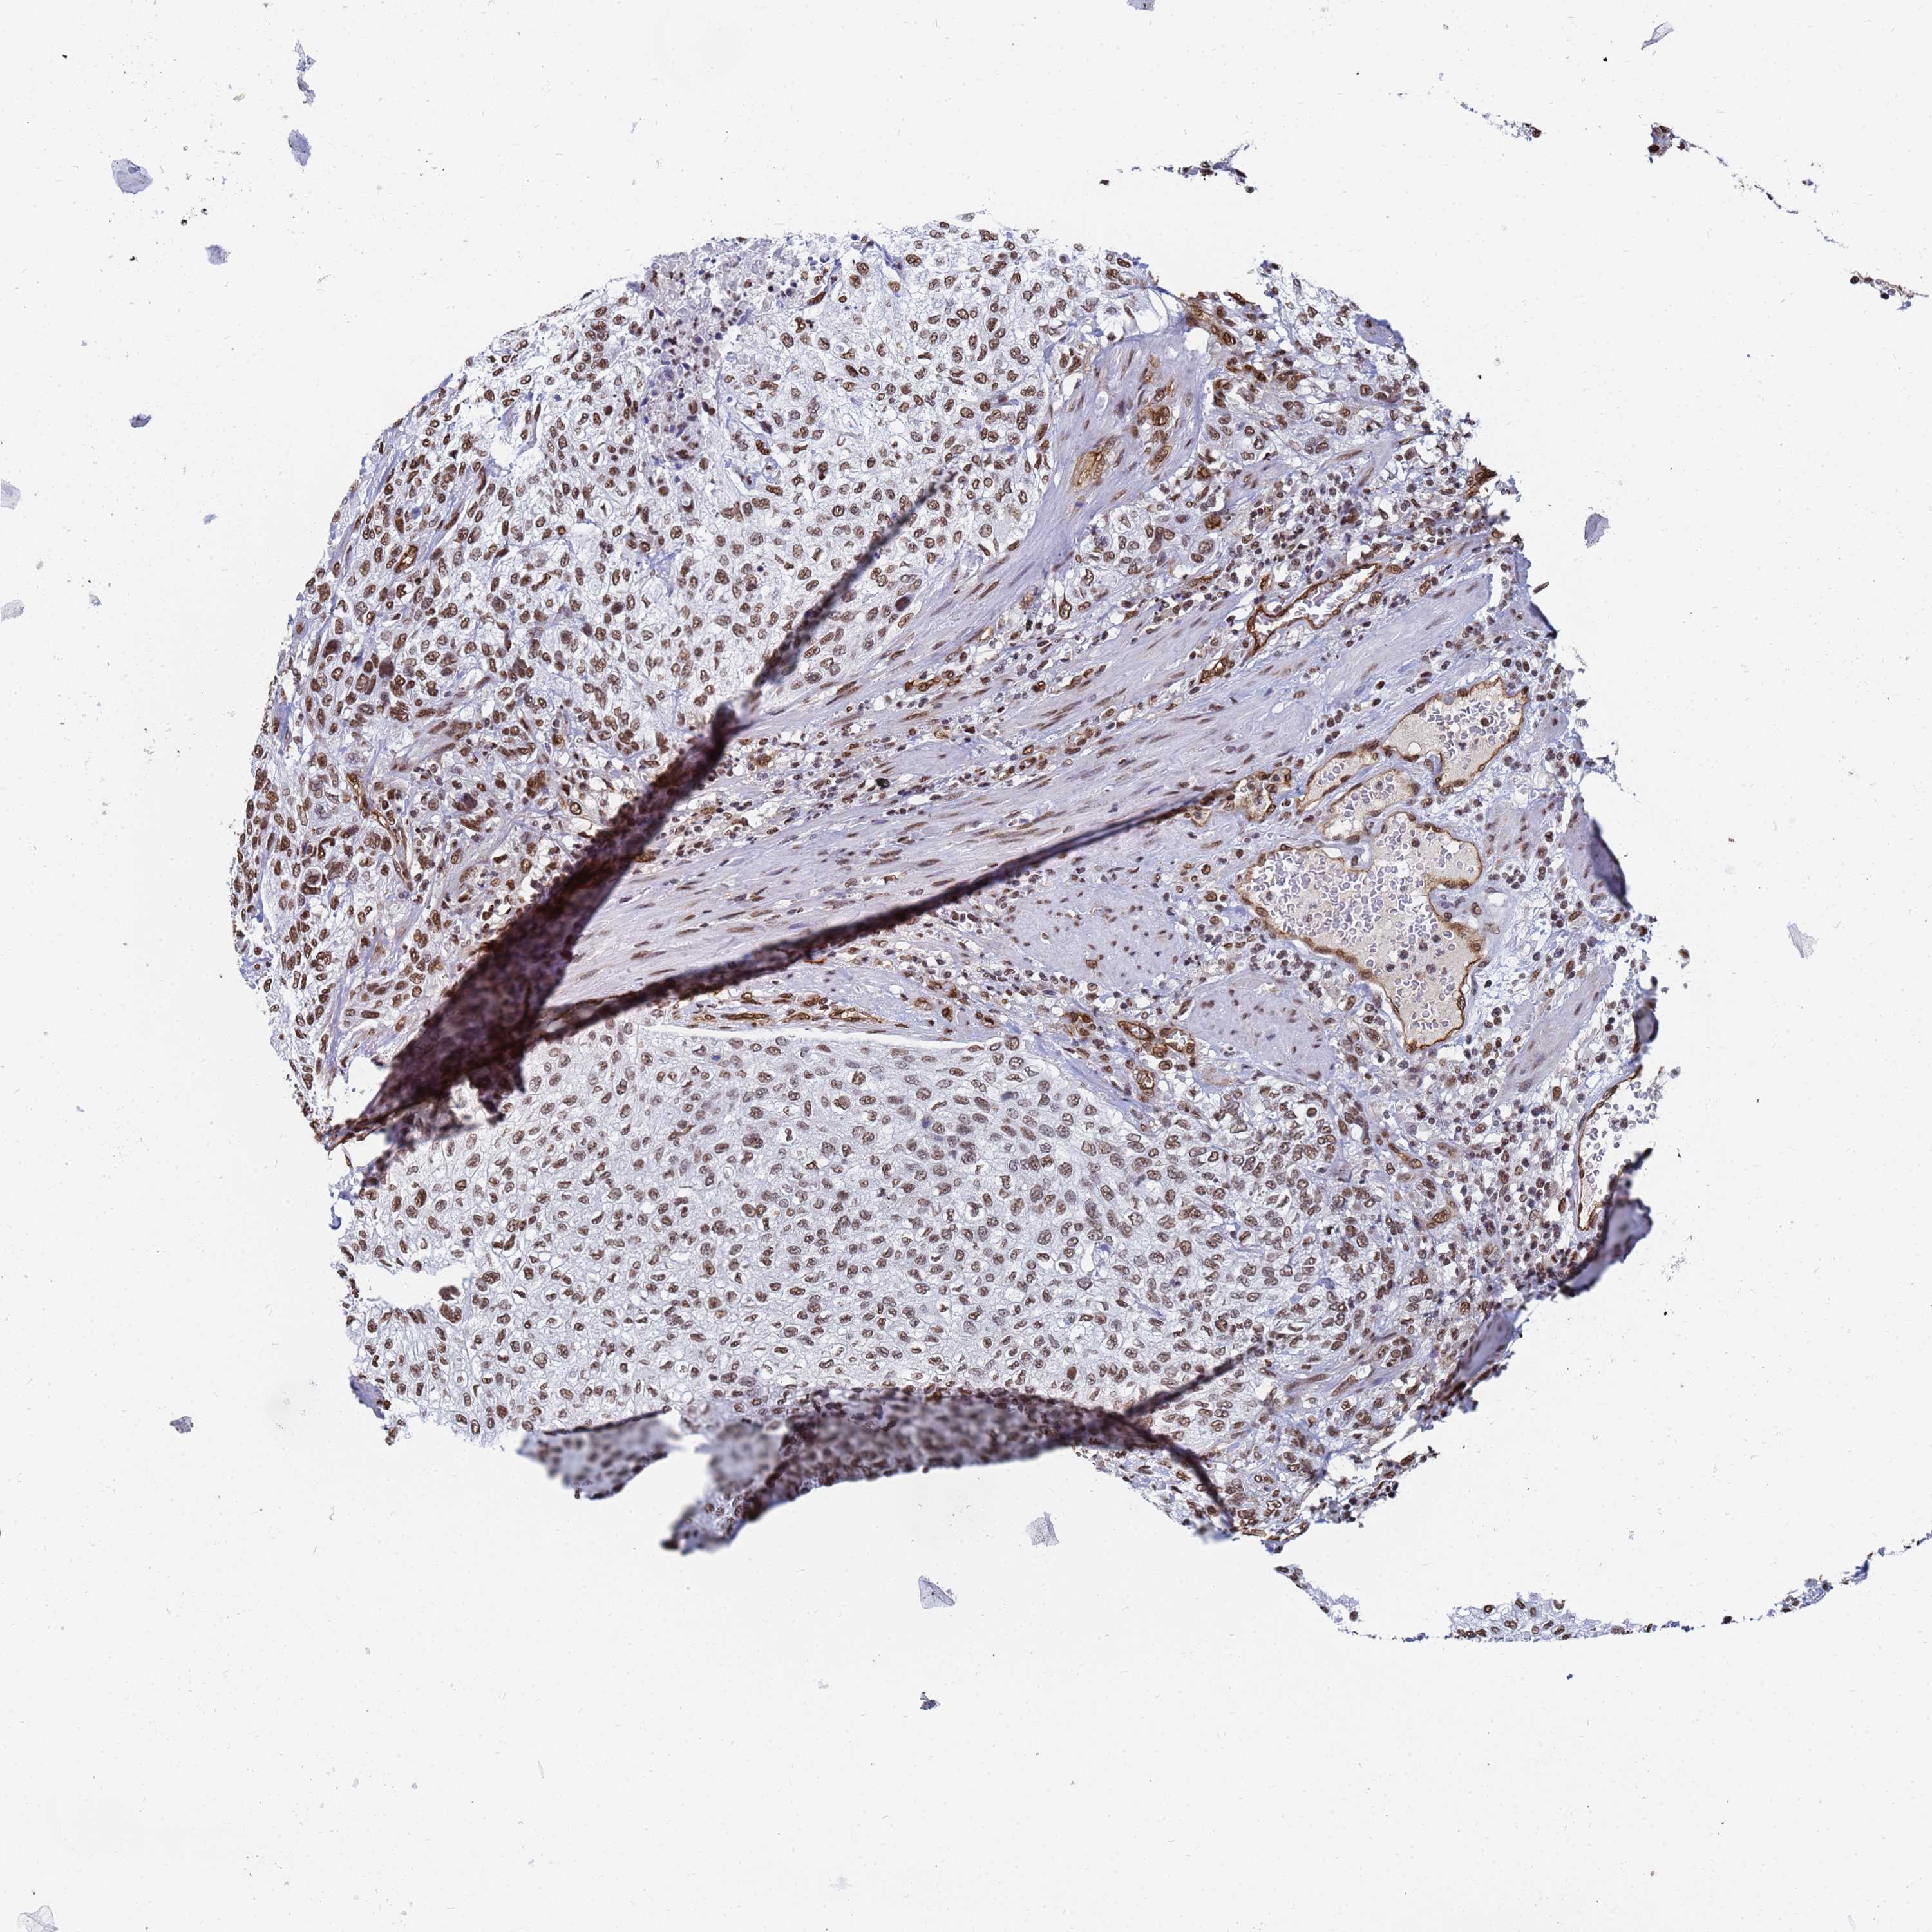

UROTHELIAL CANCER - Protein expressioni

A mouse-over function shows sample information and annotation data. Click on an image to view it in a full screen mode. Samples can be filtered based on level of antibody staining by selecting one or several of the following categories: high, medium, low and not detected. The assay and annotation is described here.

Note that samples used for immunohistochemistry by the Human Protein Atlas do not correspond to samples in the TCGA dataset.

Antibody stainingi

Antibody staining in the annotated cell types in the current human tissue is reported as not detected, low, medium, or high, based on conventional immunohistochemistry profiling in selected tissues. This score is based on the combination of the staining intensity and fraction of stained cells.

Each image is clickable and will lead to virtual microscopy that enables deeper exploration of all samples and also displays staining intensity scores, fraction scores and subcellular localization as well as patient and tissue information for each sample.

Antibody HPA045785

Staining

High

Medium

Low

Not detected

Intensity

Strong

Moderate

Weak

Negative

Quantity

>75%

75%-25%

<25%

None

Location

Nuclear

Cytoplasmic/membranous

Cytoplasmic/membranous,nuclear

Urothelial carcinoma, High grade

Urothelial carcinoma, Low grade